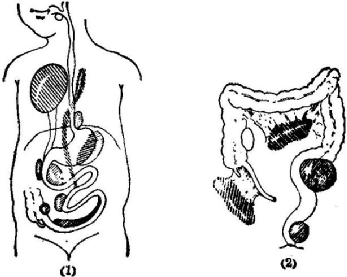

肠重复畸形是指在小肠的近系膜侧出现的一种圆形或管状结构的空腔器官,与其毗邻的小肠有相同的组织结构,其血液供应亦非常密切。是小儿常见的先天性畸形,可以发生在口腔到肛门的任何部位,以小肠多见,最常见于回肠。有的患儿伴有腹痛、呕吐、腹部包块等临床表现,还有部分小孩无任何症状,多在健康体检中发现。

undefined 上图为肠重复畸形可能出现的部位